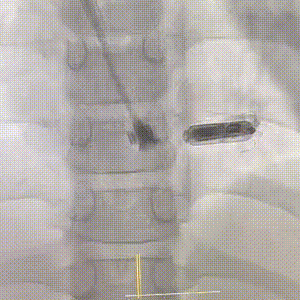

手术在全麻下进行,在超声引导下成功穿刺右侧颈内静脉,置入8F鞘管并提前置入Proglide血管缝合器。经鞘管送入导丝,稳定通路后,将Micra AV递送系统沿导丝轻柔推进,经上腔静脉、右心房进入右心室。术中采用多角度X线透视(LAO 30°、RAO 30°)及心腔内超声(ICE)辅助,精确引导递送系统定位至右室间隔中位。

提前置入 Proglide 血管缝合器